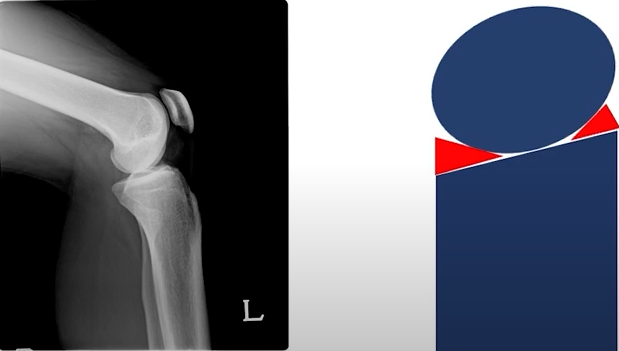

이러한 불안정성을 위해 구슬과 같은 대퇴부위를 잡아주는 해부학적 구조물이 바로 "반월연골판(Meniscus)" 입니다.

탁자위에 고무타이어를 둘러서 구슬이 안빠져나오게 한다고 생각하면 쉽게 이해할 수 있습니다.